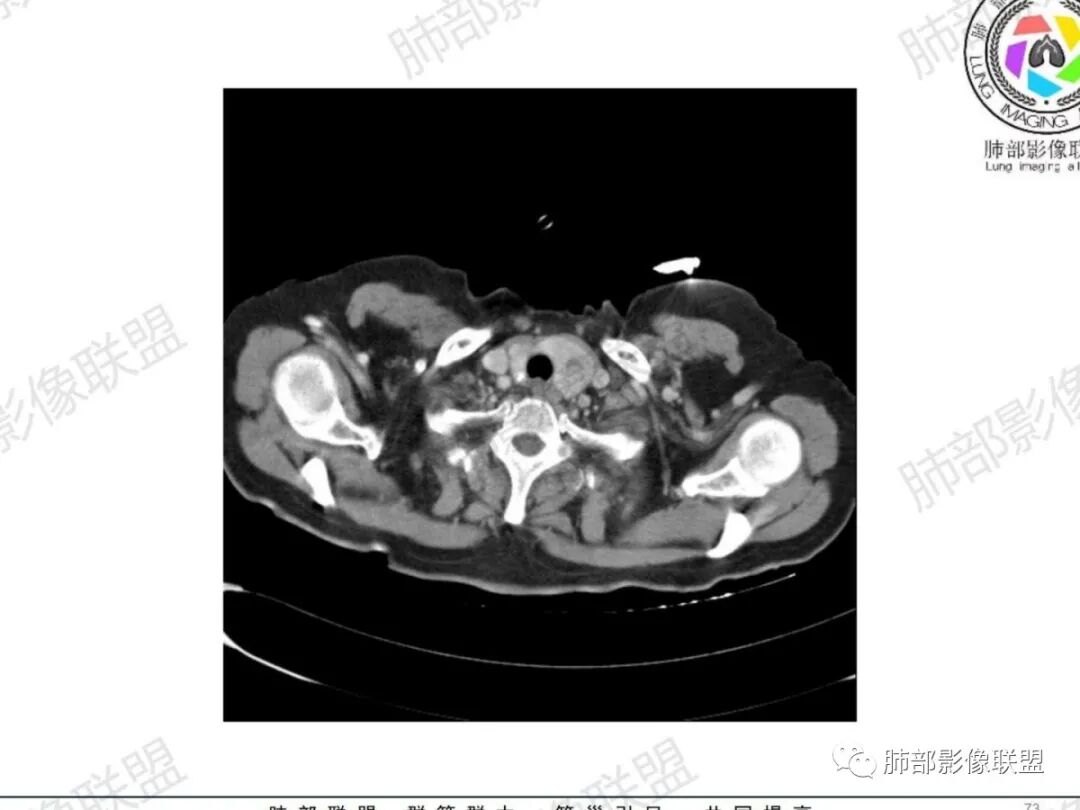

主支气管后缘外可见一实性结节,病变跨支气管管壁生长,部分突向管腔内,病变边缘光滑,平扫密度均匀,增强后尚均匀强化,纵隔淋巴结肿大不明显。

气管右后侧壁结节,结节向气管腔内突出,气管壁增厚,轻度强化,左侧甲状腺占位,考虑气管原发肿瘤,腺样囊性癌?类癌?

女,69反复咳嗽1年,胸闷二天,气管腔内见结节影,病灶突向腔内,管腔狭窄受压呈月牙状改变,增强扫描轻度强化,考虑腺癌?左侧甲状腺病变,不除外转移性病变。

从病史提示:甲状腺占位、气管占位、肺部炎症

甲状腺左叶结节边界不太清楚

甲状腺结节边界不太清楚,但是窗宽窗位不太理想,需要调至最佳状态观察才合适